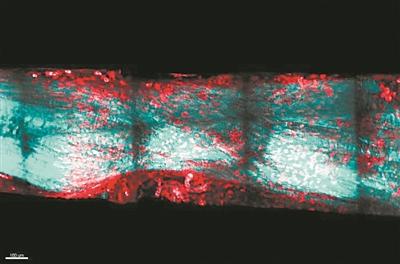

◎本報記者張佳欣提高記憶力是我們關注的永恆話題。隨着年齡的增長,人們會出現記憶力下降的現象,這是一種自然的生理規律。同時,一些疾病,如阿爾茨海默病,最常見的症狀就是記憶力減退。有沒有什麼辦法能讓人增強記憶力呢?近日,發表在《科學進展》雜誌上的一篇論文稱,神經科學家設計了一種合成蛋白質,能...

科技日報北京11月30日電(記者張夢然)蠑螈有驚人的多種組織和器官再生能力,還不會形成疤痕組織。這一能力如能用於人類,將可幫助大量受傷的人們快速康復。日本名古屋大學團隊揭示了蠑螈的肌腱再生是如何快速發生的。這項發表在《骨科研究雜誌》上的成果,比較了蠑螈和其它哺乳動物的再生機制。哺乳動物的器官...